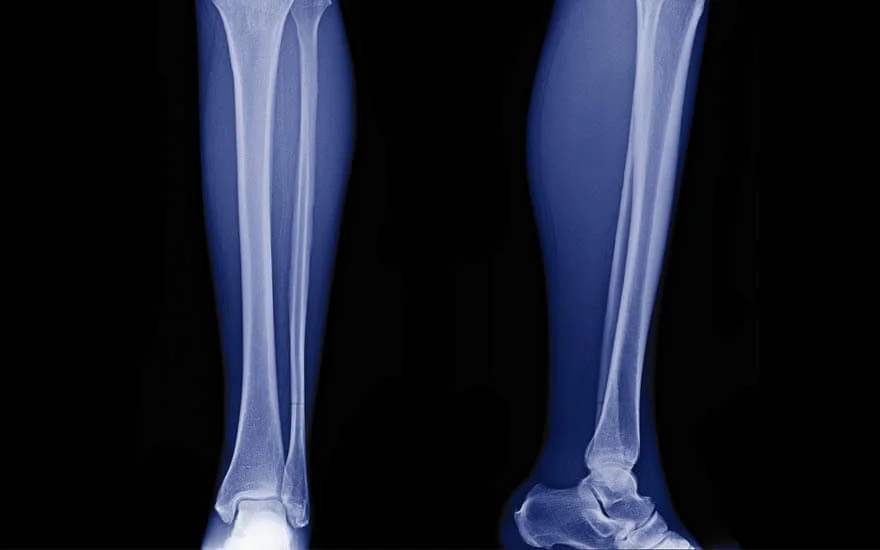

Shin splints

Shin splints refer to shin pain, i.e., pain from your shin bone (tibia), which runs along the front of your leg. Applying ice packs for up to 20 minutes several times daily and avoiding activities that trigger your shin splints can help ease the pain. This may mean switching from running on hard surfaces like the road to running on softer surfaces, such as a treadmill, grass, dirt, or synthetic running tracks.

To reduce your risk of developing shin splints, stretch properly before and after your run and wear supportive running shoes.

Stress fractures

Stress fractures are small cracks in your bones that cause pain, swelling and tenderness. In runners, they commonly occur in the lower leg bone (tibia), upper leg bone (femur) and bones in the feet (metatarsals).

If you have stress fractures, you must stop the activity causing them, or your fractures could worsen and fail to heal correctly. Treatment includes rest, avoiding both low- and high-impact exercises, and applying ice packs for up to 20 minutes several times daily. If you have a severe stress fracture, you may need surgery.

To prevent stress fractures, wear well-fitting running shoes, gradually increase the intensity and length of your runs, and alternate your running with non-impact activities, such as swimming or using a cross-trainer. Also, ensure your diet includes enough calcium and vitamin D — if you’re concerned, talk to your doctor or a dietitian about supplements.